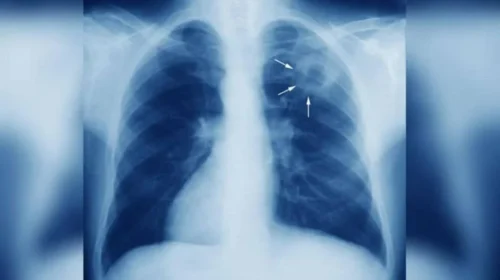

Η φυματίωση μεταδίδεται πολύ εύκολα με τα σταγονίδια του αέρα, συνήθως όταν κάποιος που νοσεί βήχει. Τα βασικά συμπτώματα που πρέπει να μας βάλουν σε υποψίες είναι:

Αν η κατάσταση ξεφύγει, η λοίμωξη δεν μένει μόνο στους πνεύμονες, αλλά μπορεί να κάνει ζημιά και σε άλλα όργανα του σώματος.